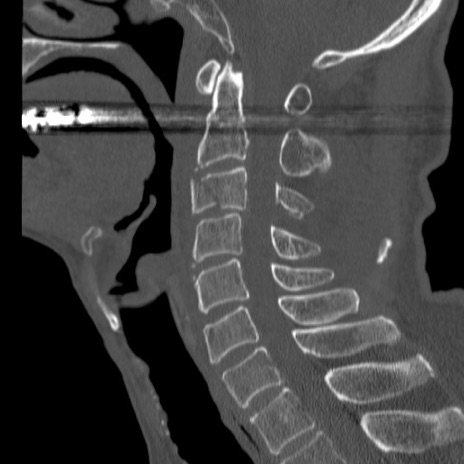

症例46 頚椎CT(矢状断像)

【症例】80歳代男性

【主訴】両側頚部〜上肢のしびれ

【現病歴】昨日、自宅内で転倒、その後より上記症状あり。意識障害なし。

【身体所見】両側上肢のallodynia(熱痛覚過敏)あり。MMTおよびDTRは正確な所見取れず。両上肢の挙上はなんとか可能。

異常所見と診断は?